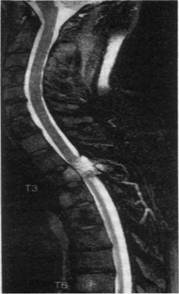

Классификация. Опухоли спинного мозга разделяют на интрамедуллярные (вну-тримозговые) и экстрамедуллярные (вне вещества спинного мозга). Экстрамедуллярные опухоли по отношению к твердой мозговой оболочке в свою очередь делят на субдураль-ные (под оболочкой) и экстрадуральные (над оболочкой). Экстрамедуллярные опухоли составляют 80 %, а интрамедуллярные - только 20 % всех опухолей спинного мозга. У 52 % больных встречаются экстрамедуллярные субдуральные опухоли, у 28 % - экстрамедуллярные экстрадуральные.

В зависимости от локализации выделяют опухоли шейного отдела спинного мозга (18% всех опухолей спинного мозга), грудного (66 %), поясничного (15 %), крестцового (1 %). Опухоли спинного мозга могут быть первичными и вторичными - метастатическими. Метастатические опухоли - это экстрадурально расположенные метастазы рака или саркомы легких, рака грудной железы, рака предстательной железы, почек, а также миелома и лимфома.